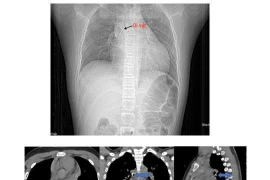

Bé 13 tuổi nguy hiểm tính mạng vì đinh ghim sắc nhọn rơi vào đường thở

Bệnh viện Phổi Trung ương đã thực hiện thành công ca nội soi phế quản gắp đinh ghim dài 2,5 cm mắc sâu trong phế quản của bé trai.